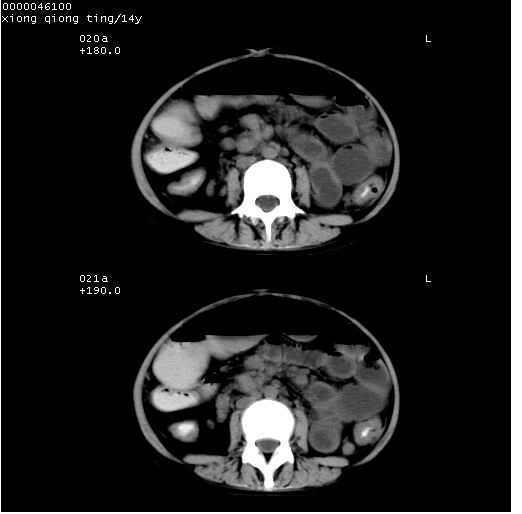

患儿 女,14岁。不规则发热一周,偶感头痛,无抽搐及呕吐。pe:神清,精神差,双侧瞳孔等大等圆,对光反射敏感,双肺未闻及明显啰音,心音有力,腹部触之似揉面感,下腹压痛,无反跳痛。

腹部b超提示:子宫缩小,盆腔积液,肝实质回声密集。

临床诊断:发热原因待查:1)腹部结核感染。2)伤寒?3)结缔组织病?

中下腹及盆腔ct轴位平扫+增强扫描(层厚10mm,螺距1.0,重建间隔10mm),图像如下:

(注:患儿检查当日上午9时口服胃肠道对比剂,下午3时许行ct扫描检查,未行对比剂直肠保留灌肠,检查当日患儿腹泻)

中下腹及盆腔ct轴位扫描(ps+ce)提示:腹部肠管明显充气扩张,并见数个不同宽度之气液平面;疑不全性肠梗阻或肠郁张。临床会诊考虑为患儿腹泻,肠郁张所致;后来未经特殊处理,患儿大便恢复正常,亦无腹胀。

临床出院诊断:1)结核性腹膜炎。2)腹膜后淋巴结结核。3)脂肪肝。